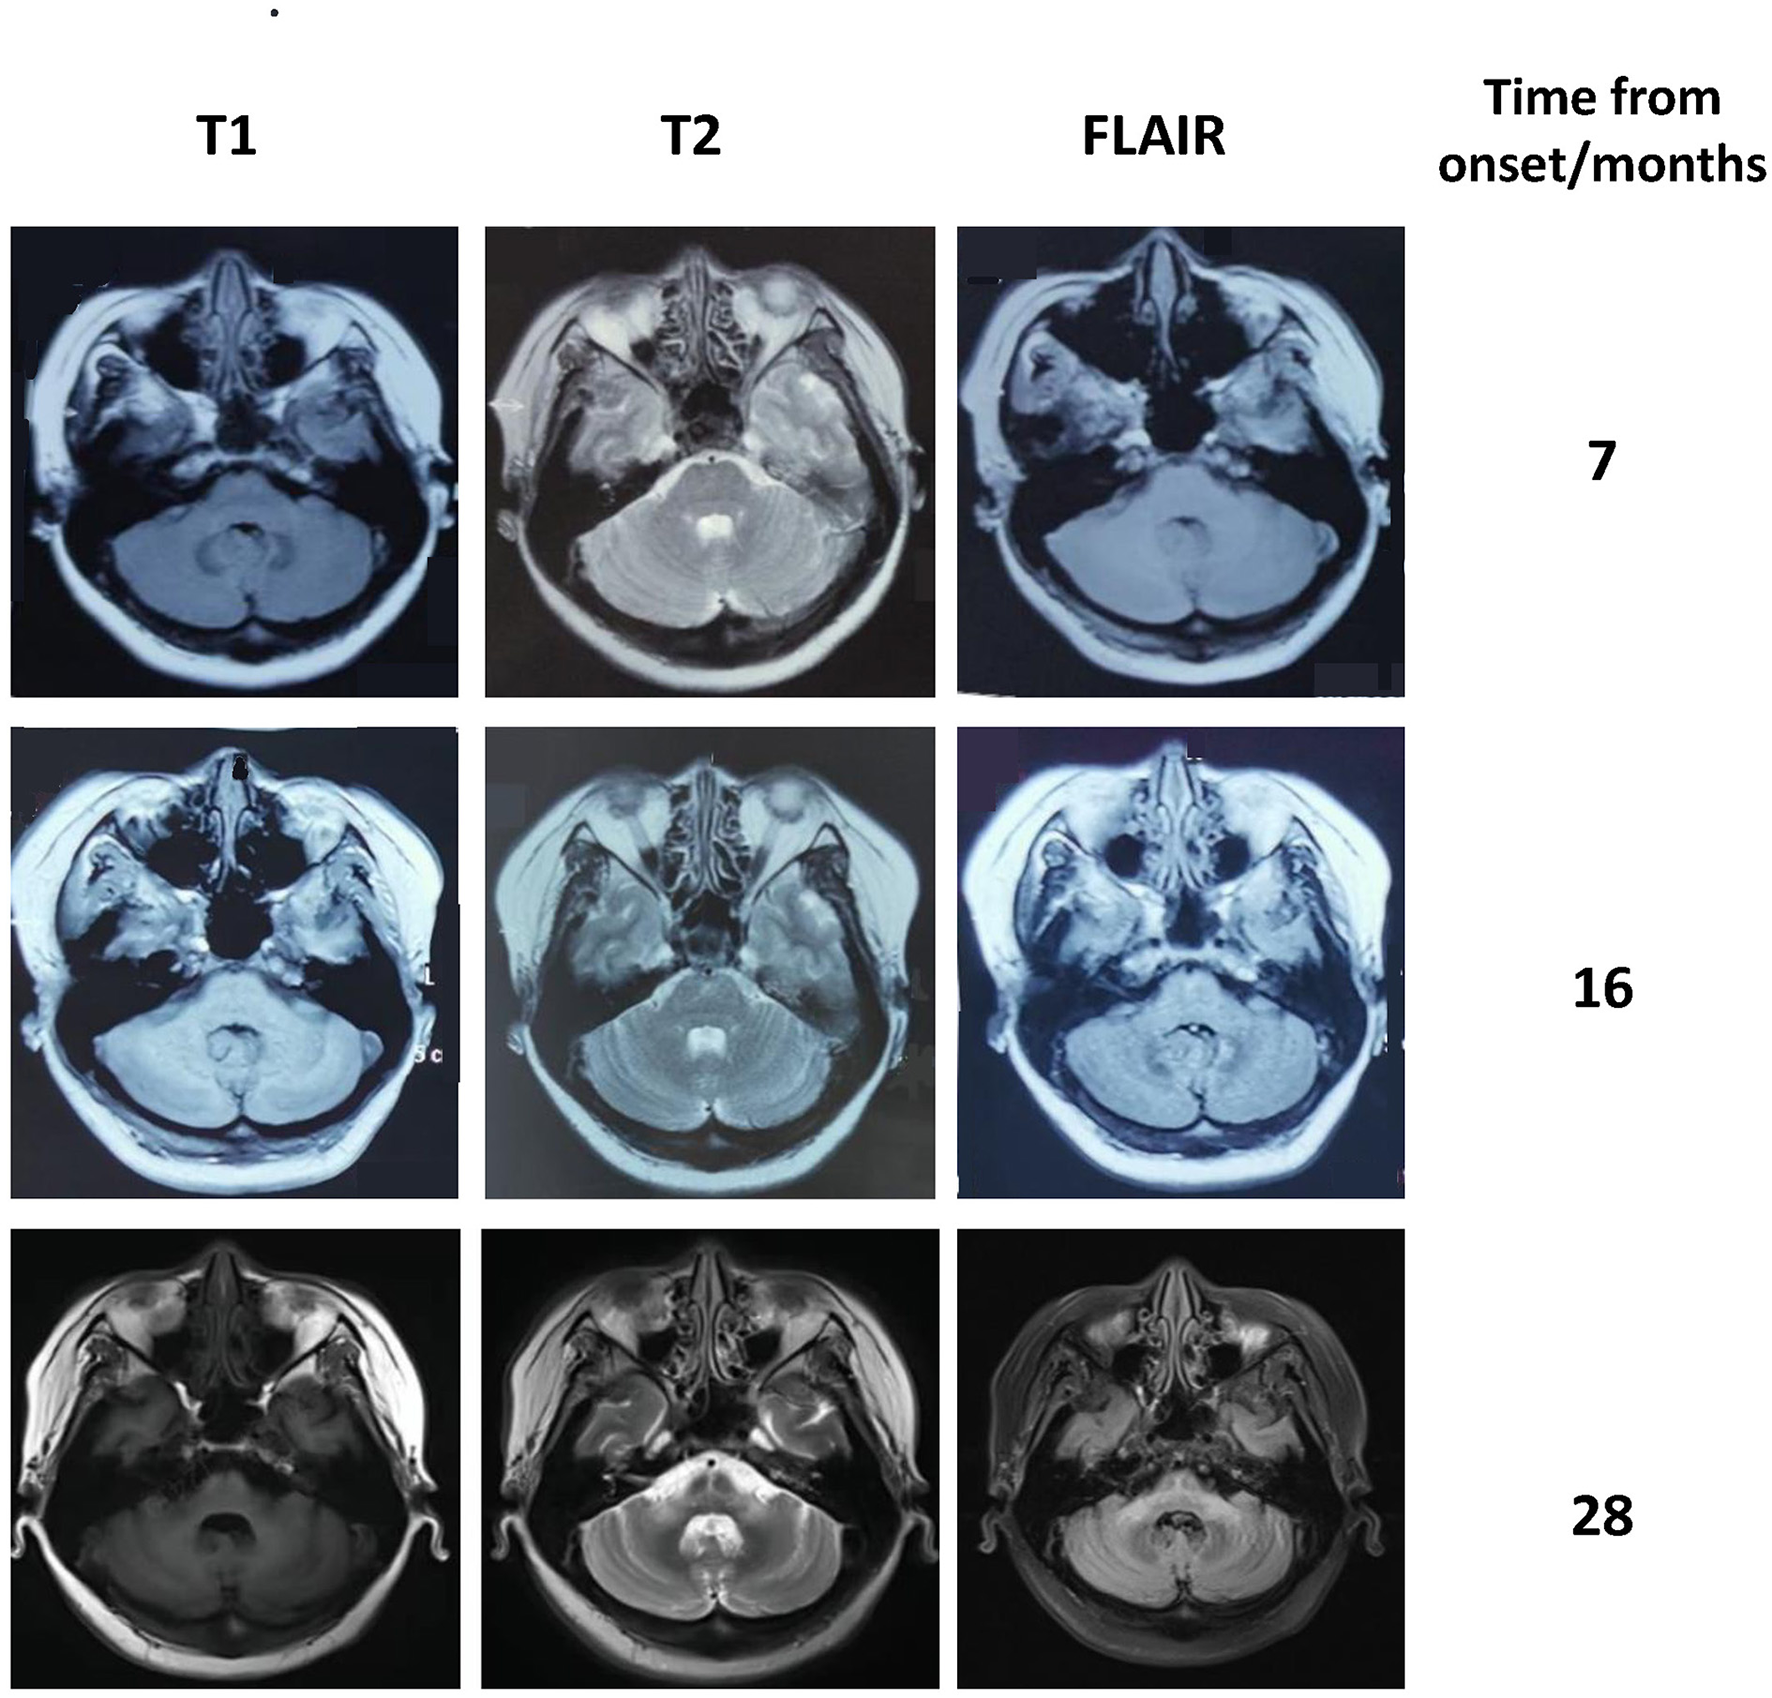

Figure 1

Brain MRI of our patient showing progressive atrophy of the cerebellum and the middle cerebellar peduncle. The hot cross bun sign and the abnormal signal in the middle cerebellar peduncles became more pronounced over time.

A 40-year-old woman presented with paresthesia and weakness in all four limbs for 2 years and an unstable gait for 1 year. Electromyography conducted 7 months after the disease onset showed neurogenic change, while brain MRI performed was unremarkable. Ganglioside antibodies in the serum and cerebrospinal fluid (CSF) were both negative. Empirical corticosteroids significantly improved her symptoms. However, the numbness and quadriplegia reappeared during corticosteroid weaning 4 months later, and she gradually developed dizziness, an unsteady gait, and diplopia. Brain MRI performed at 16 months after the disease onset revealed T2 hyperintensity in the middle of the pons (Figure 1). There was no improvement with pulse glucocorticoid therapy and intravenous immunoglobulin, and she developed slurred speech and dysphagia.

The patient was diagnosed with PNS with breast carcinoma. Endocrine therapy with goserelin and letrozole and plasma exchange were performed. However, her neurological symptoms worsened. Follow-up brain MRI revealed the HCBs, with signal change in the bilateral middle cerebellar peduncles and widened cerebellar sulci (Figure 1). Her symptom was stabilized by a repeated course of corticosteroid and mycophenolate mofetil treatment, after which CSF pleocytosis improved (white blood cell count, 2 cells/ul). However, CSF oligoclonal bands and anti-Ri in the serum and CSF remained positive. Her modified Rankin Scale score evaluated 34 months after the disease onset was 4. The clinical course of the patient is summarized in Figure 2.